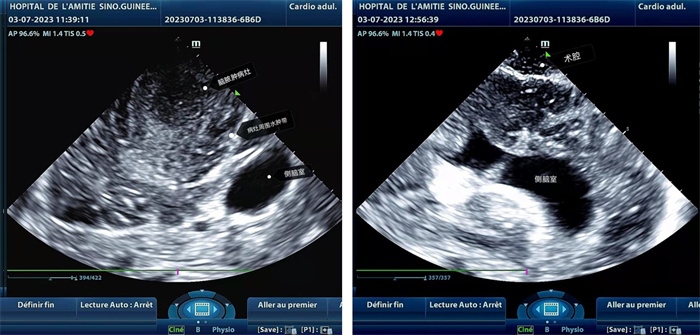

左圖顯示術(shù)中超聲見囊實(shí)性病變,大小約為4x4x3cm,病灶周圍腦組織水腫明顯;右圖為病灶切除后,術(shù)中超聲示術(shù)腔無病變殘留

左圖顯示術(shù)中超聲見囊實(shí)性病變,大小約為4x4x3cm,病灶周圍腦組織水腫明顯;右圖為病灶切除后,術(shù)中超聲示術(shù)腔無病變殘留。中國(guó)第二十九批援幾內(nèi)亞醫(yī)療隊(duì)供圖